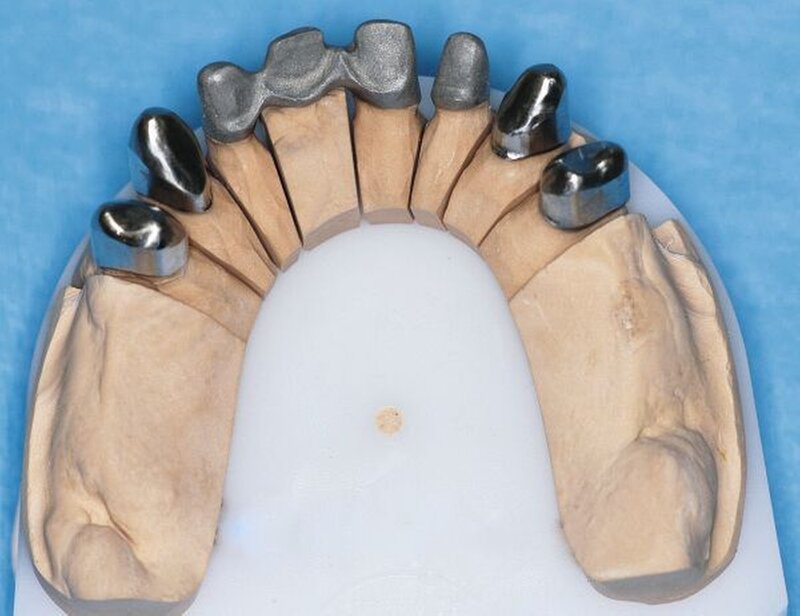

Die Abformungen des OK und des UK erfolgten als Korrekturabformung unter Verwendung eines A-Silikons. Zur Darstellung der subgingival liegenden Präparationsgrenzen wurden mit Adstringentien getränkte, geflochtene Retraktionsfäden in die Sulci aller Zähne eingelegt. Eine adäquate Trocknung der abzuformenden Bereiche wurde durch die Verwendung von Kompressions-Wattekappen, die auf den einzelnen Zähnen platziert wurden, durch Parotispflaster sowie durch eine konstante Absaugung erreicht. Um ein möglichst langes Verarbeitungsintervall zu erzielen, wurde das verwendete Silikon zuvor im Kühlschrank gelagert [Wöstmann et al., 1992; Wöstmann et al., 1999]. Nach erfolgter Abformung wurde ein Gesichtsbogen zur individuellen Übertragung des Oberkiefermodells in den Artikulator angelegt, danach wurden die Provisorien des I- und IV-Quadranten wieder befestigt. Nun wurden partielle interokklusale Registratschlüssel mithilfe eines intraoral anwendbaren Autopolymerisats im Bereich des II- und III-Quadranten angefertigt und beschliffen. In einem zweiten Schritt wurden die Provisorien im I- und IV-Quadranten entfernt und die partiellen interokklusalen Registratschlüssel des II- und III-Quadranten eingesetzt. In dieser Position wurden nun ebenfalls Registratschlüssel im I- und IV-Quadranten angefertigt und beschliffen. Durch dieses Vorgehen war es möglich, die im Rahmen der Registration ermittelte Position – unter Einbeziehung der präparierten Zahnhartsubstanz – auf die Modellsituation des Arbeitsmodells zu übertragen. Abschließend erfolgte die Farbauswahl. Die Arbeitsmodelle wurden mithilfe des zuvor angelegten Gesichtsbogens und der erstellten Registratschlüssel in einen teiljustierbaren Artikulator übertragen. Im Labor erfolgte die Herstellung der Nichtedelmetall-Gerüste der Einzelkronen 22, 32, 31, 41 und 42, die der Brücken 12 bis 21, 35 bis 37 und 43 bis 46 sowie die der Nichtedelmetall- Primärkronen 13, 14, 23 und 24.

In einer weiteren Sitzung erfolgten die Gerüstanproben der angefertigten Restaurationen. Alle Provisorien im Ober- und im Unterkiefer wurden entfernt und die präparierte Zahnhartsubstanz versäubert. Danach wurde die Passgenauigkeit der hergestellten Gerüste am Patienten überprüft. Dies erfolgte unter Verwendung einer Häckchensonde sowie eines niedrigviskösen Silikons. Zudem wurden die mechanische Stabilität, die Friktion und die technische Gestaltung überprüft.